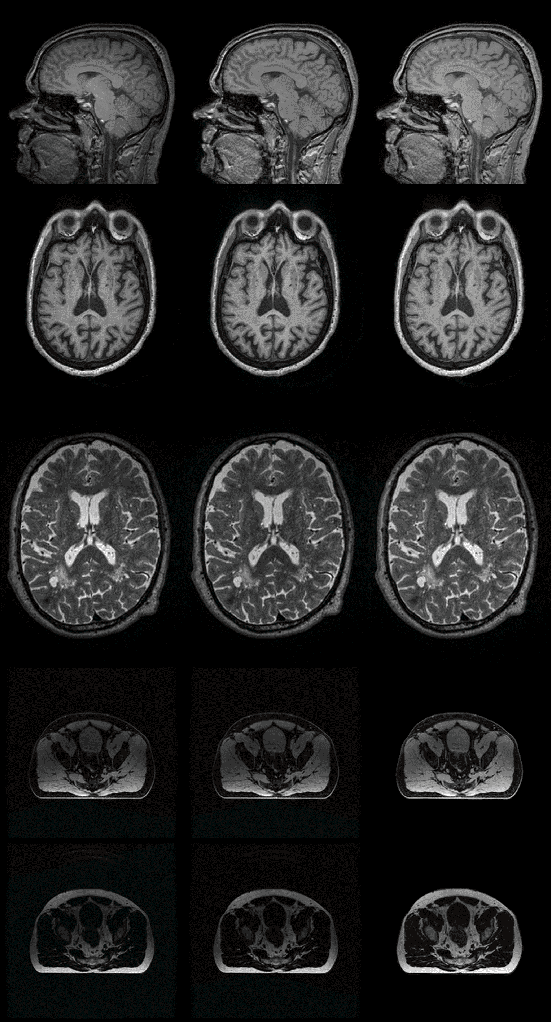

Abstract:In recent years, deep neural networks for image inhomogeneity reduction have shown promising results. However, current methods with (un)supervised solutions require preparing a training dataset, which is expensive and laborious for data collection. In this work, we demonstrate a novel zero-shot deep neural networks, which requires no data for pre-training and dedicated assumption of the bias field. The designed light-weight CNN enables an efficient zero-shot adaptation for bias-corrupted image correction. Our method provides a novel solution to mitigate the biased corrupted image as iterative homogeneity refinement, which therefore ensures the considered issue can be solved easier with stable convergence of zero-shot optimization. Extensive comparison on different datasets show that the proposed method performs better than current data-free N4 methods in both efficiency and accuracy.